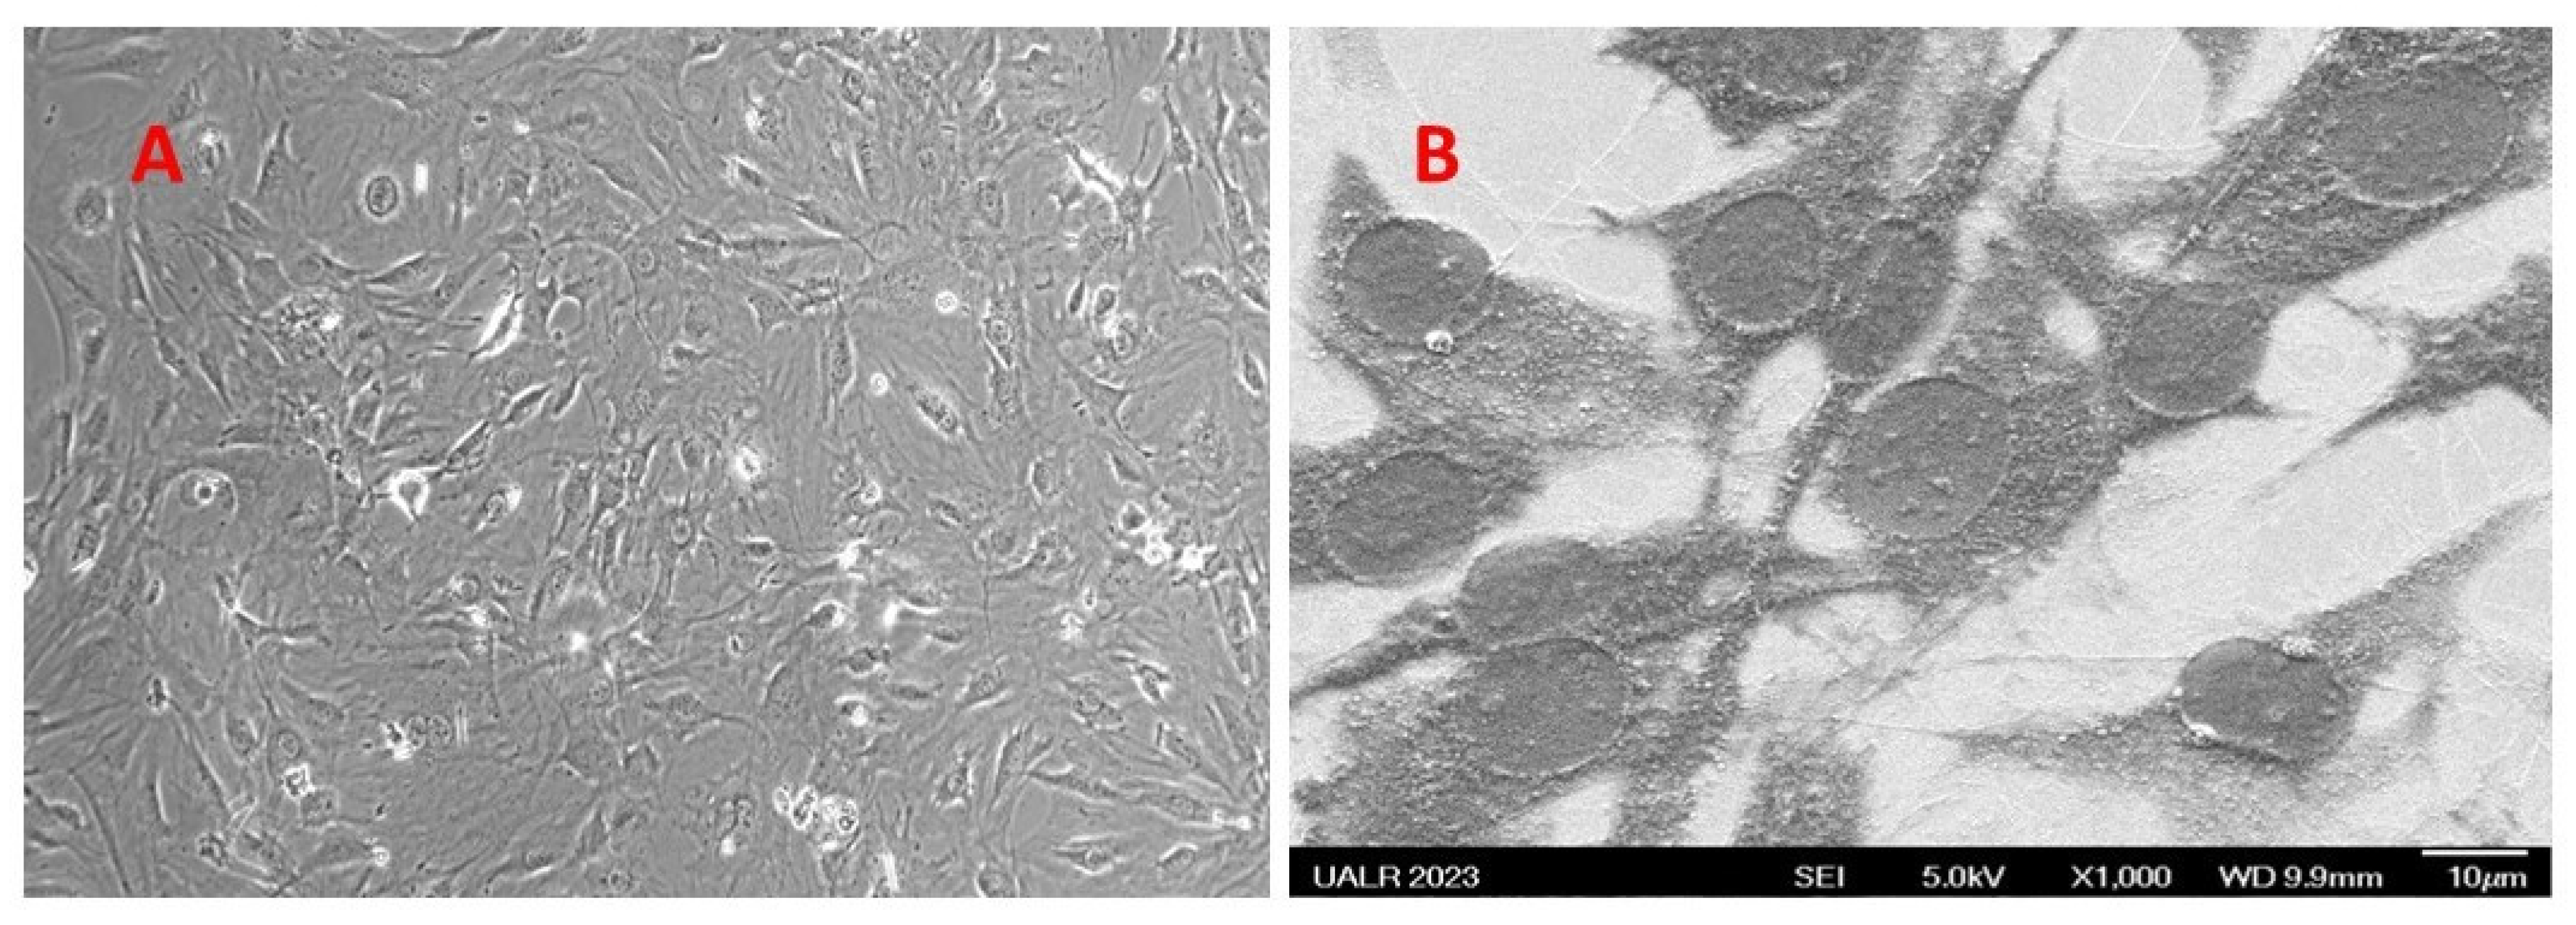

3.3. Biocompatibility Study